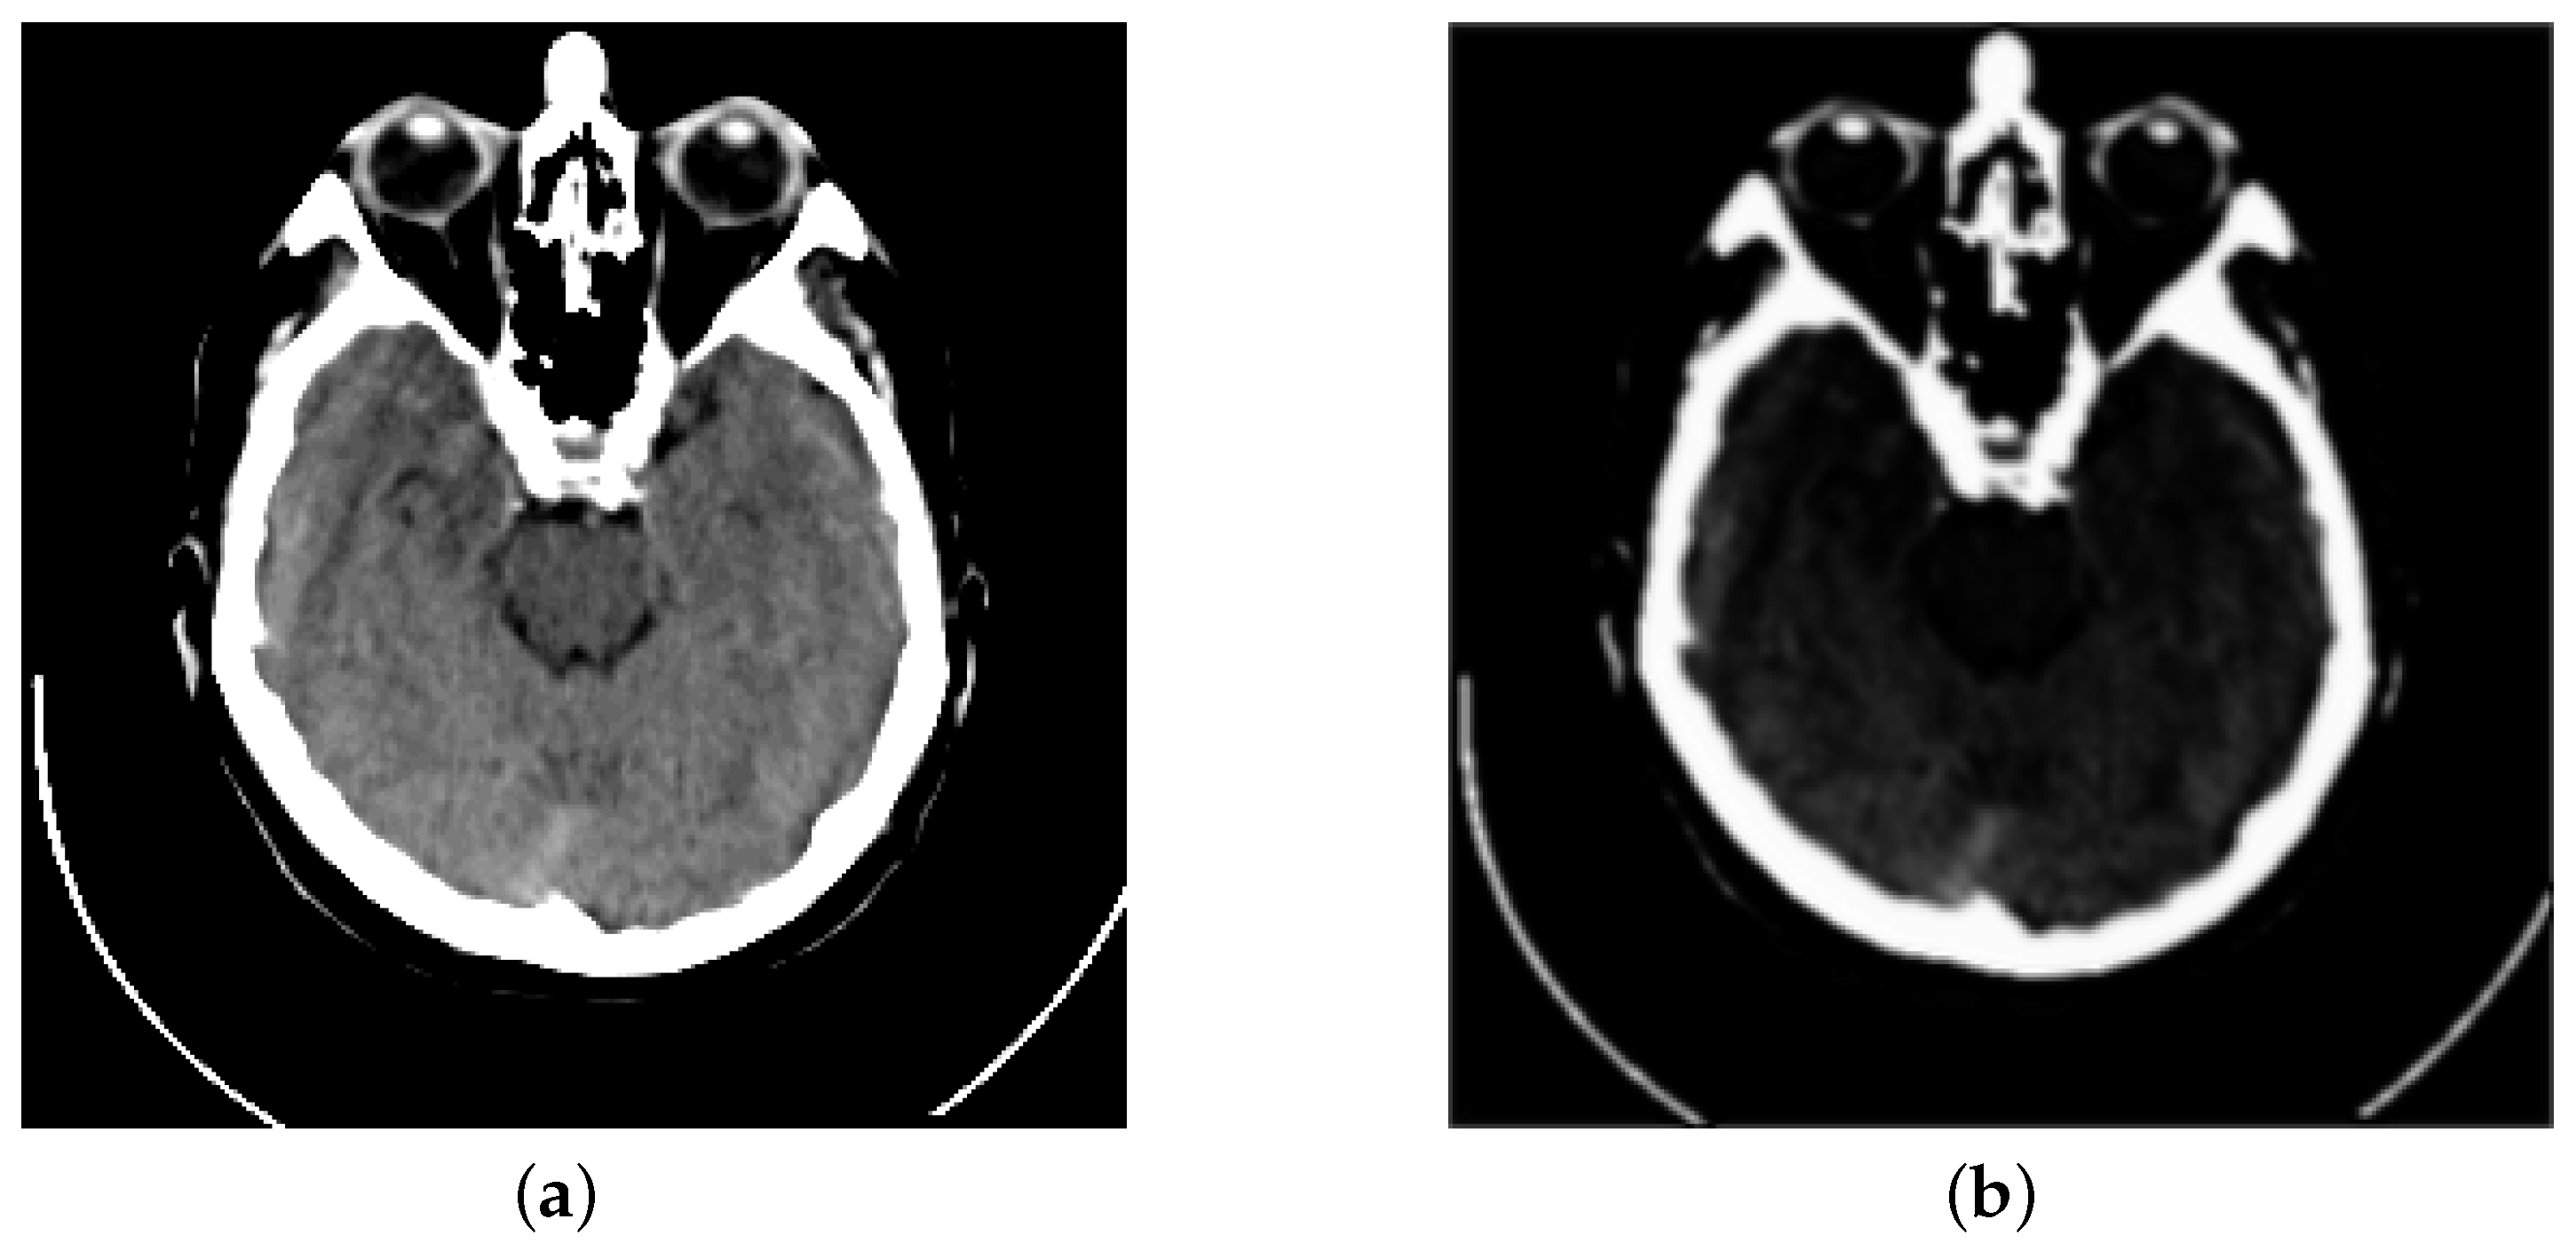

Inspired by previous works, we propose a fusion strategy, which is based on the visual saliency-based method (VSM) [34]. We use VSM to calculate the weight maps of computed tomography (CT) images. Then, based on these CT image weight maps we obtain the weight maps of magnetic resonance imaging (MRI) images. Figure 1 presents the visual saliency map of CT image on the image pair “Acute stroke speech arrest-3”. It is obviously observed that VSM of CT can remain the features of dense structures such as implants and bones. Meanwhile, the low-resolution soft tissues are reduced.

Figure 1.

Example of a CT image and its visual saliency map. (a) The source CT image of “Acute stroke speech arrest-3”. (b) The visual saliency map of this CT image.